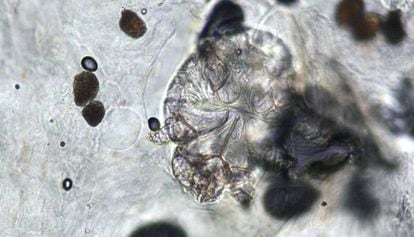

Un total d'11 alumnes, professors i algun familiar de l'escola de Sant Llorenç Savall (Vallès Occidental) estan afectats per un brot de sarna diagnosticat dos dies després d'un altre que va afectar una vintena de persones grans i una altra vintena de treballadors de la residència geriàtrica pública del mateix municipi.

Encara que es desconeix l'origen del brot, l'episodi infecciós s'ha produït uns dies després que una vintena de treballadors i una altra vintena d'interns de la residència de gent gran pública de la mateixa localitat es veiessin afectats també per un brot de sarna. En aquest cas, els afectats ja han rebut tot el tractament per aturar la malaltia, que ha mantingut de baixa els treballadors afectats i aïllats els interns. Una empresa especialitzada va netejar divendres a fons totes les habitacions i zones comunes de la residència geriàtrica pública.